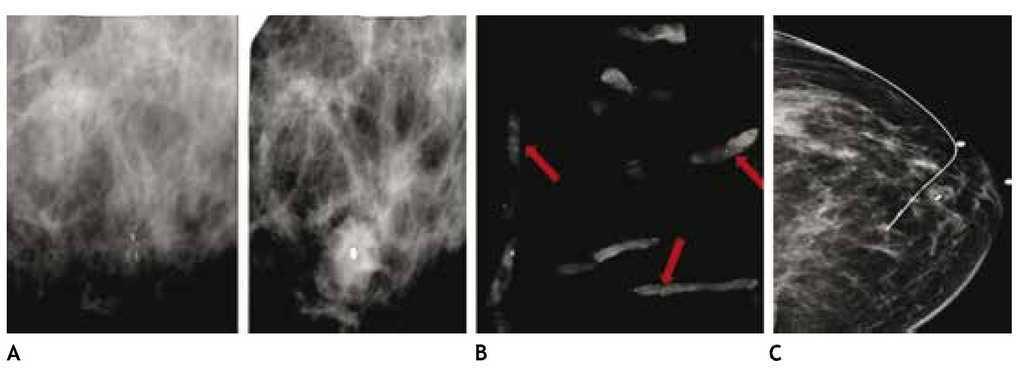

El carcinoma ductal in situ (CDIS), se presenta comúnmente con microcalcificaciones agrupadas en el 62% a 72%9 (figs. 2A-D) y gracias a esta tecnología su frecuencia relativa ha aumentado en los últimos años, así como la detección de lesiones precursoras o limítrofes como la hiperplasia ductal con atipia (fig. 3).

Figura 2 A), B) y C) Paciente de 48 años, asintomática, calcificaciones agrupadas polimorfas con distribución segmentaria CSED (flechas). D) ultrasonido, tumoración mixta, BIRADS 5: cáncer ductal in situ de alto grado.

Figura 3 Asintomática, paciente de 41 años con grupos de microcalcificaciones polimorfas izquierdas de distribución lineal (flechas), BIRADS 4C: hiperplasia ductal con atipia.

En estas lesiones no palpables, es de gran utilidad la estereotaxia, sistema utilizado ya sea en la mastografía analógica como en la digital, para efectuar la biopsia precisa y exacta, generalmente de microcalcificaciones, mediante pistolas de corte aspiración y vacío, con la paciente sentada o en la mesa prona (figs. 4A y B).